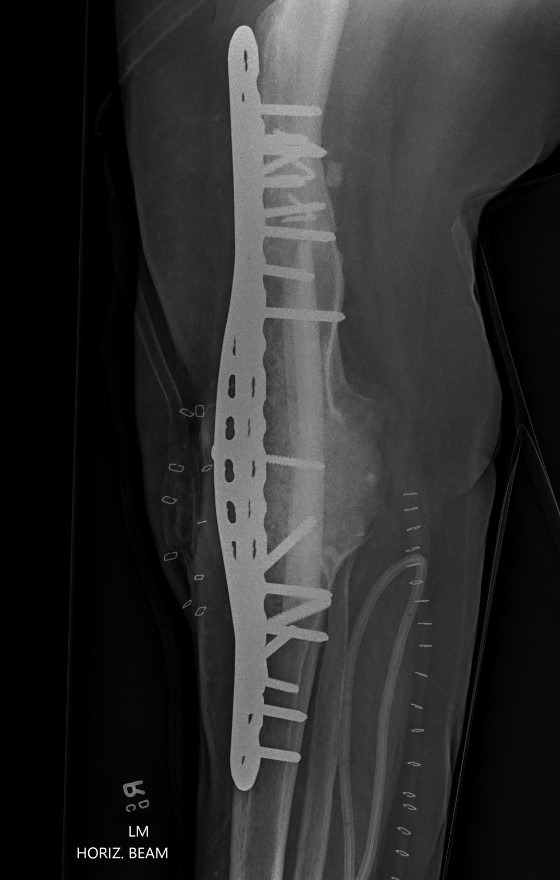

Dual plates